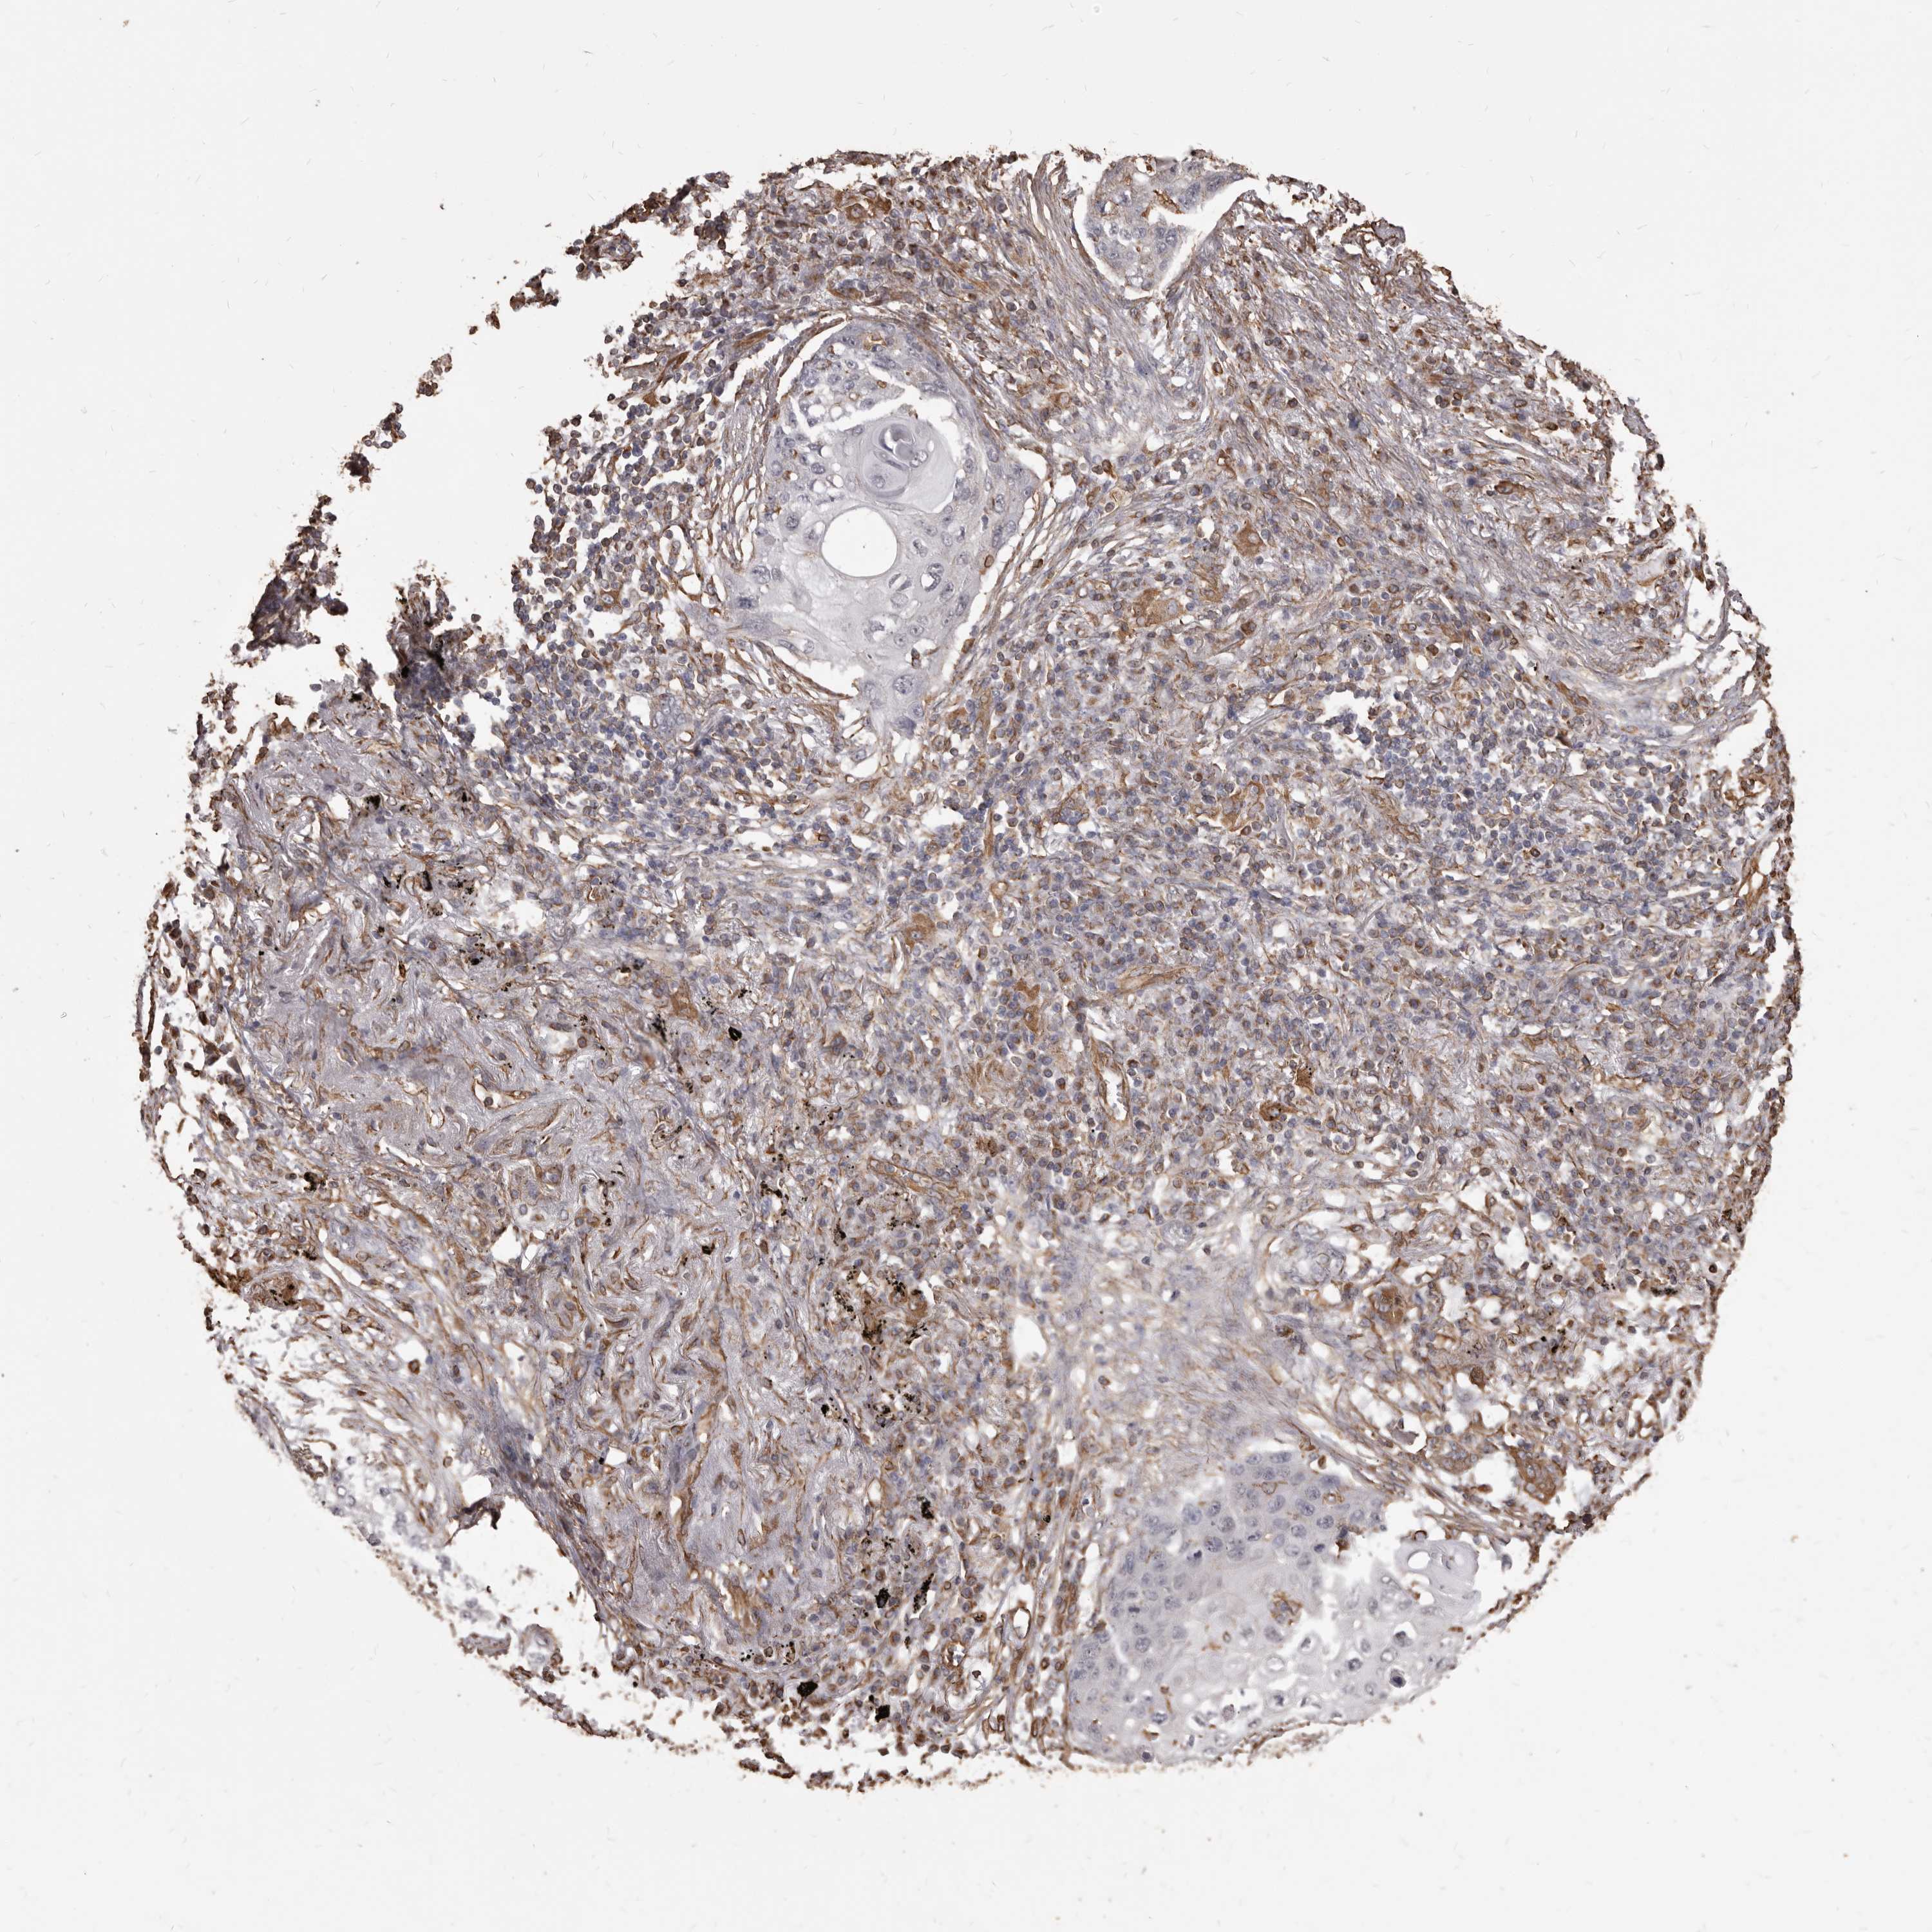

CANCER LUNG CANCER Show tissue menu

Lung cancer

Human cancer